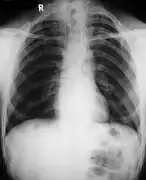

- Poor development of the clavicles and a bell-shaped rib cage in a person with CCD